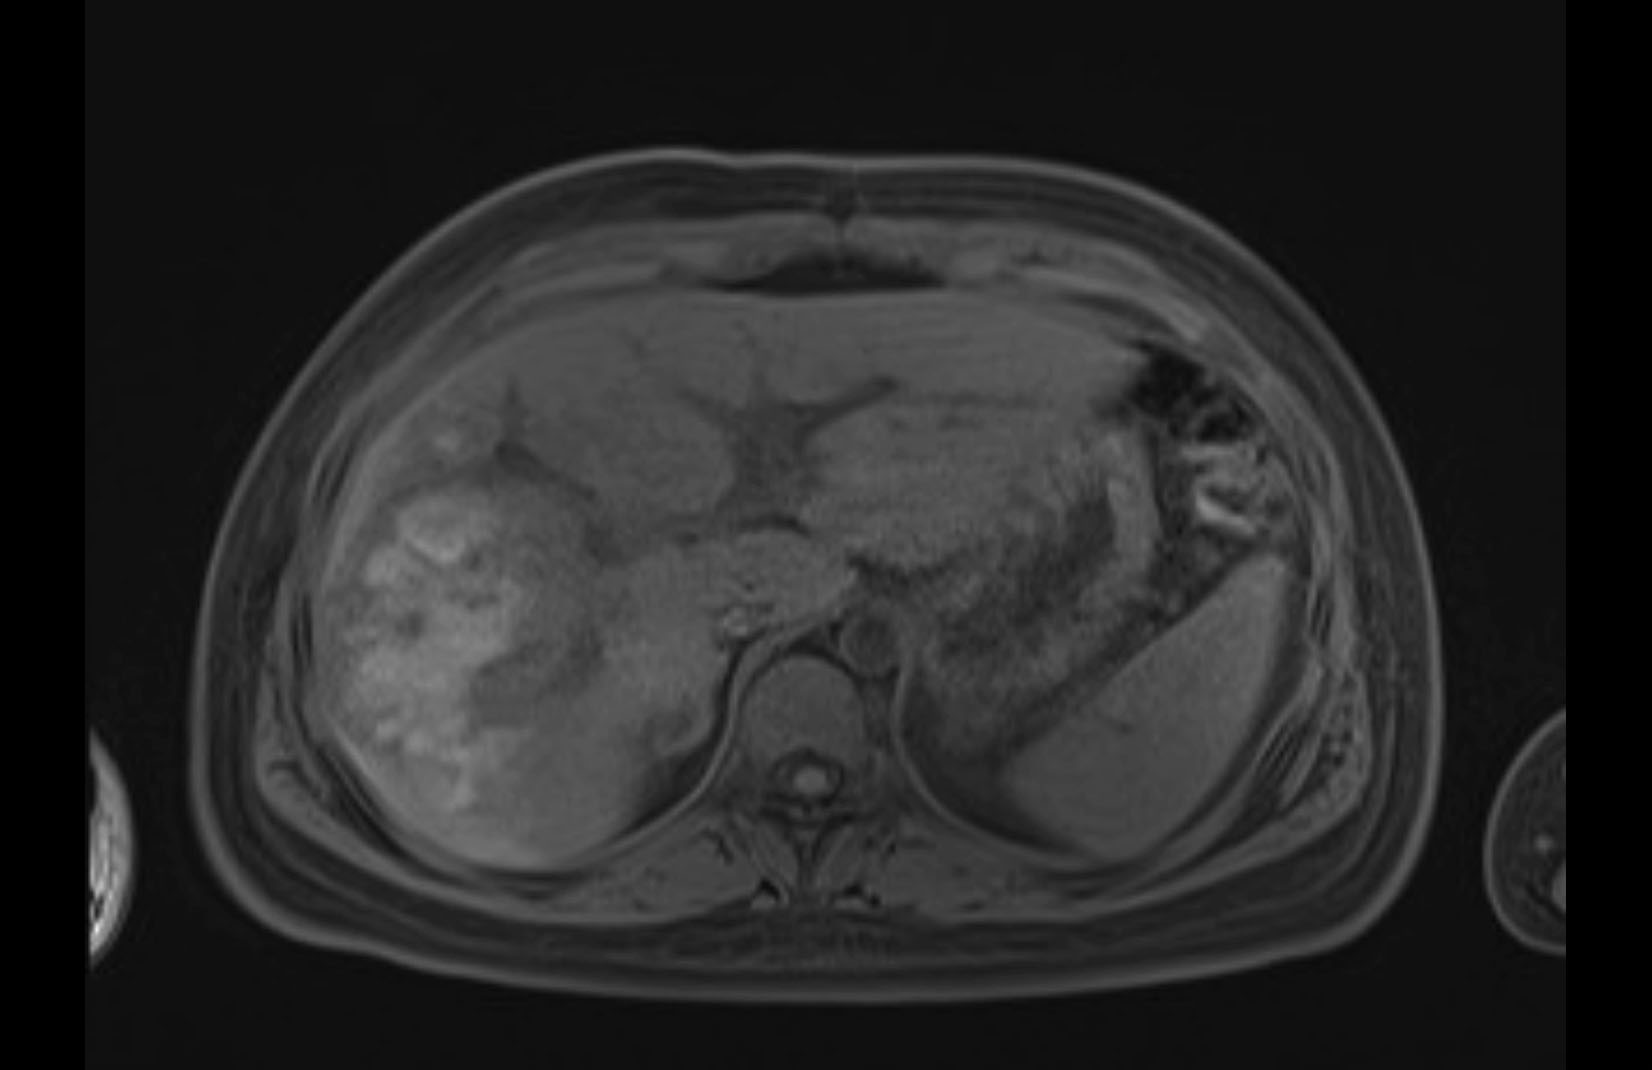

Imaging Analysis

Look through the patient's CT scan to identify any areas of concern for the necessary procedure.

MRI T1

MRI T2

Based on initial findings, which issue(s) would you be most concerned about?